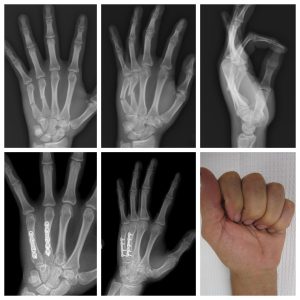

Metacarpal Fractures

Metacarpal Fracture ORIF